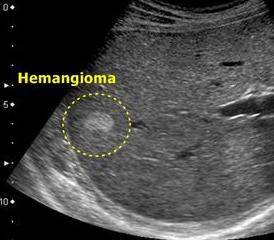

- 2) При помощи УЗИ метода хорошо видны образования с четко очерченными границами.

- Ультразвуковое исследование (УЗИ) печени. Данный метод является одним из самых доступных в первичном определении опухоли. Чаще всего опухоль представлена образованием округлой формы, имеющим четкие контуры и границы, которые легко заметны на мониторе компьютера при обследовании. При выявлении данного заболевания с помощью УЗИ, больному необходимо дополнительно пройти обследование КТ или МРТ.

Чаще всего заболевание обнаруживается на УЗИ. Такое исследование помогает не только найти опухоль, но и определить ее тип и стадию развития. Другие методы диагностики: